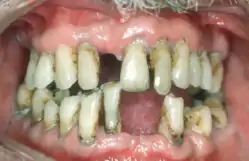

Periodontal disease, also known as gum disease, is a set of inflammatory conditions affecting the tissues surrounding the teeth.[5] In its early stage, called gingivitis, the gums become swollen and red and may bleed.[5] It is considered the main cause of tooth loss for adults worldwide.[7][8] In its more serious form, called periodontitis, the gums can pull away from the tooth, bone can be lost, and the teeth may loosen or fall out.[5] Bad breath may also occur.[1]

Symptoms | Red, swollen, painful, bleeding gums, loose teeth, bad breath[1] |

Complications | Tooth loss, gum abscess[1][2] |